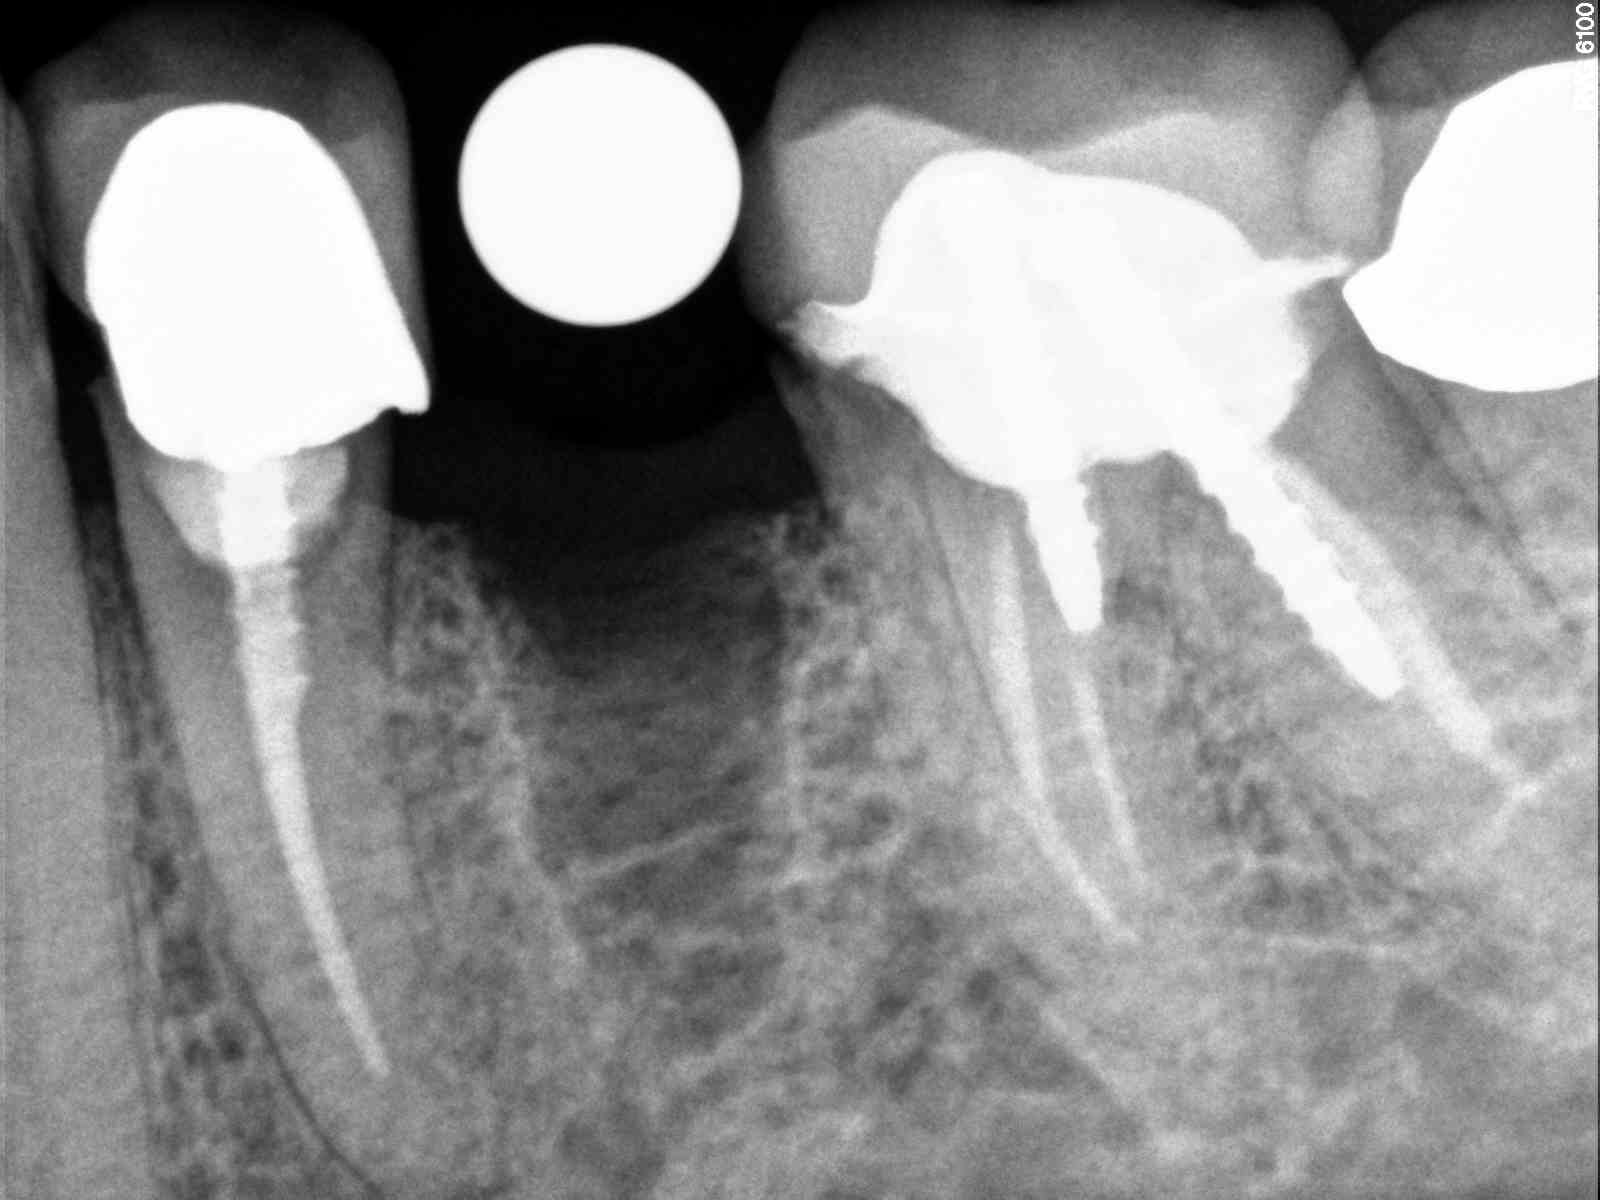

| This is a NP that found me online for implants. Much of her dental work looks similar to the crowns adjacent to this area |